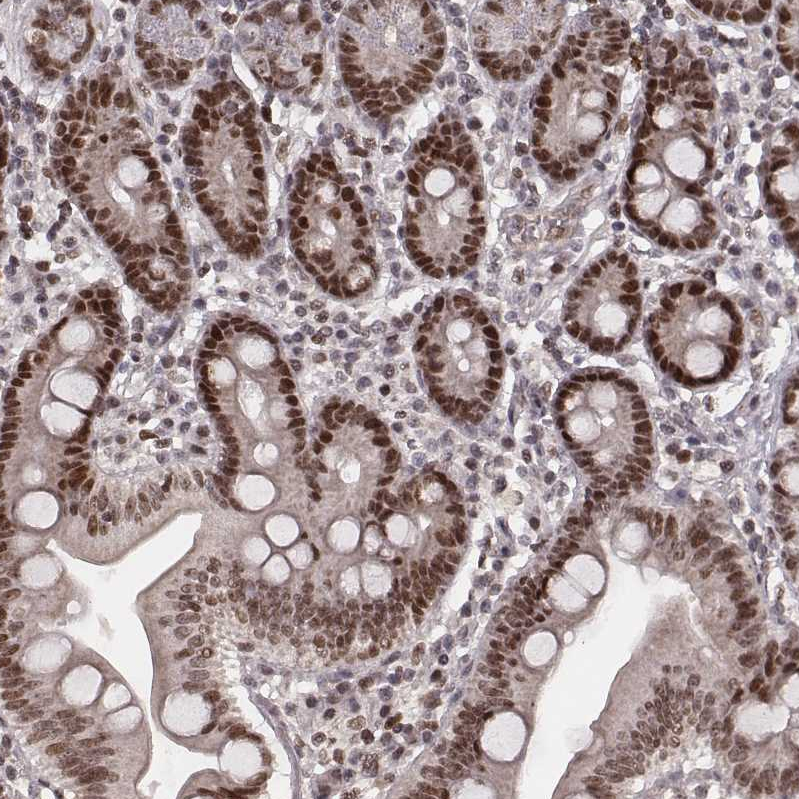

Immunohistochemical staining of human testis shows strong nuclear positivity in cells in seminiferous ducts.